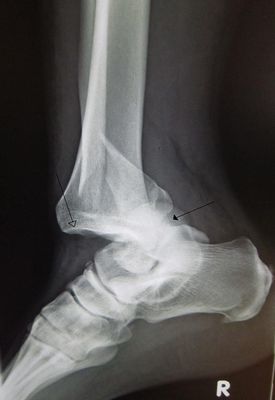

¿Que Tipo De Patología Consideras Que Es?

Esquince

Fractura

Luxación

Hernia Discal